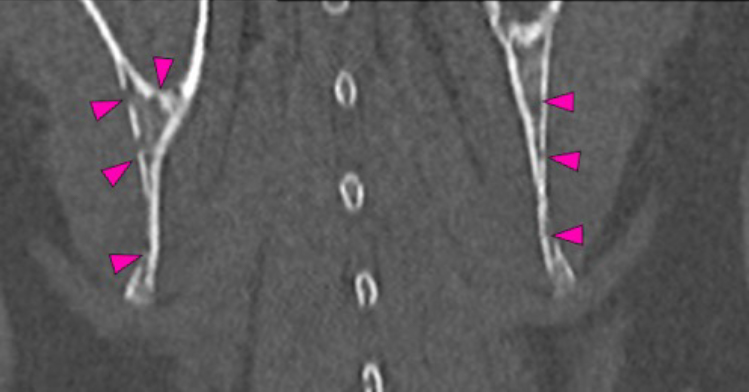

There are multiple osteolytic lesions with the same characteristics affecting both scapula and the pelvic bones included (pink and blue arrows respectively). There are osteolytic lesions with the same characteristics affecting multiple ribs. Associated with these lesions, there are multiple rib fractures.

In both coxofemoral joints partially included, there is severe flattening of both acetabula (orange arrows), with marked incongruity of the joint, with dorsal displacement (subluxation) of both femoral heads (blue arrows). In addition, there is severe periarticular new bone formation affecting both acetabula, femoral heads and necks.